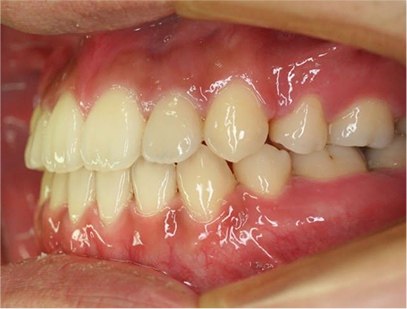

治療後

• 左側

治療前の写真と治療後の写真を比べると口元が治療前は下唇が出ていて、鼻の下が凹んでいました。上顎の前歯のデコボコも綺麗に並びました。また、上下の前歯は開咬が治りしっかりと咬み合ってます。

治療期間は患者様の協力が大変に良かったために2年半とさほど長くはありませんでした。

• 口元が綺麗になった事、上下の前歯が咬み合った事、八重歯が改善された事。